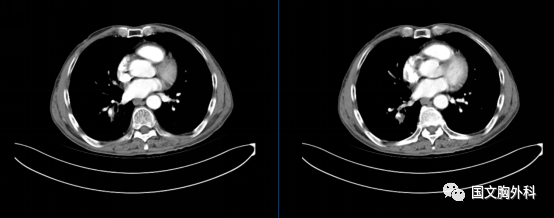

治療后↓

患者于吉林國文醫(yī)院順利完成右肺下葉切除術(shù)手術(shù)治療,保留了右肺的中葉。

更幸運的是原先肺癌切下來后,顯微鏡下都找不到癌細胞,這真是奇跡。來到國文醫(yī)院診療,真是得病后不幸中的萬幸。